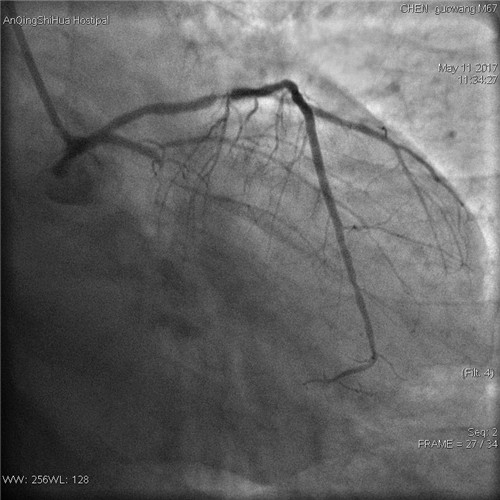

術(shù)前 回旋支完全閉塞

術(shù)前 前降支支架內(nèi)80%局限性再狹窄